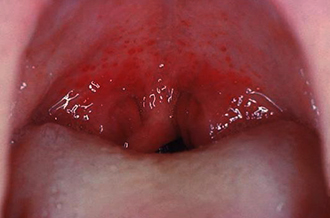

Ярко-красный цвет и появление на фоне отечной покрасневшей слизистой оболочки указывают на острый воспалительный процесс. Важно отметить внезапное возникновение симптомов и отсутствие прыщиков на горле ранее. В норме слизистая оболочка глотки имеет спокойный розовый цвет, который иногда может приближаться к красному. Поэтому для уверенности в наличии гиперемии следует осматривать горло ребенка, когда он здоров. Это поможет заметить покраснение при инфекции или убедиться в отсутствии воспаления.

Прыщи на слизистой оболочке задней стенки глотки в период острого воспаления:

- ярко-красные;

- отечные;

- увеличенные;

- четко выраженные;

- слегка приподнятые.

Эти образования располагаются беспорядочно, могут встречаться группами или на значительном расстоянии друг от друга, без четкого ограничения определенной зоны. Слизистая оболочка также становится красноватой, отекает и покрывается слизисто-гнойными выделениями.

При осмотре можно заметить утолщение слизистой оболочки, на которой присутствует слизь в виде островков с неровными краями. На фоне покраснения выделяются округлые или вытянутые красные образования — гипертрофированные фолликулы или гранулы, которые часто принимают за прыщики. Эти образования расположены на задней стенке глотки, но могут встречаться и на боковых стенках. Наблюдается отек фолликулов и значительное увеличение их размеров.